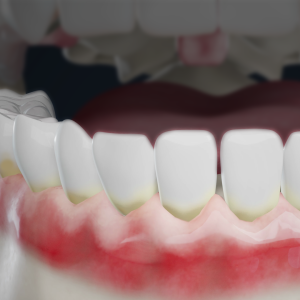

Deep Grooves in Teeth: How Sealants Protect Against Cavities

Dental fissures are deep grooves in the teeth that trap food and bacteria. Learn how sealants protect these areas and